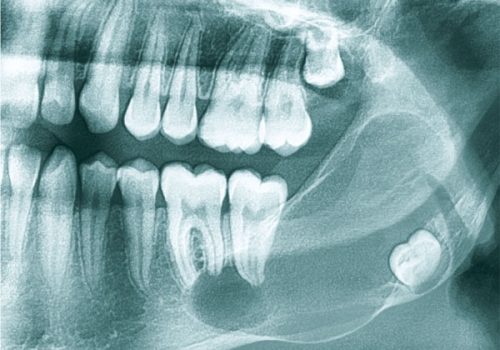

Odontogenik kistlər çənədə ən çox rast gəlinən törəmələrdən olub, başlanğıcını diş orqanından götürür. Bu törəmələr epitel hüceyrə qatı ilə döşənmiş zarla əhatə olunmuş, daxilində isə spesifik maye yerləşən kisəni xatırladırlar. Odontogenik kistlər ya xroniki iltihab nəticəsində ya da inkşaf anomaliyası nəticəsində yarana bilir.

İnkşafı və böyüməsi tədricən baş verdiyindən, bu proses pasiyent tərəfindən demək olar ki hiss edilmir. Yalnız törəmənin ciddi ölçülərə çatması nəticəsində və ya iltihablanması nəticəsində meydana çıxan kliniki əlamətlər nəticəsində aşkarlanır. Əksər hallarda isə çəkilən diş və çənə rentgen şəkillərində təsadüfən rast gəlinir.